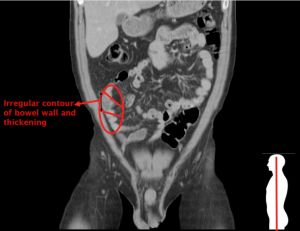

電腦斷層為優先考量,可能發現腸道變厚(wall thickening),周邊腸系膜脂肪的成股相紋(stranding),結腸憩室(Diverticula)。嚴重者可能會發現瘺管(fistula)或是腫瘍(abscess)。